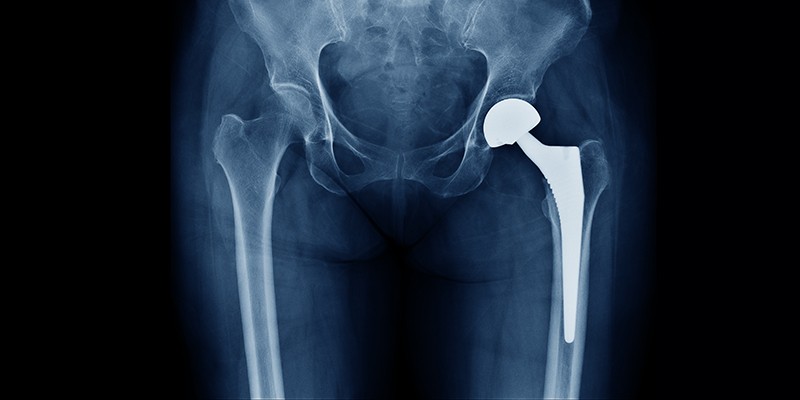

Het eindstadium van coxartrose leidt vaak tot een heupprothese. Een operatie is over het algemeen effectief. Dit onderzoek laat zien, voornamelijk op basis van nationale registraties, dat 58% van de heupprotheses na 25 jaar nog in situ is.

© Shutterstock

Evans et al. bekeken in hun onderzoek 44 case series, met in totaal 13.212 totale heupproheses (THP’s). Daarnaast gebruikten ze de data uit nationale protheseregistraties, met gegevens van 215.676 THP’s.

Uit de case series bleek een levensduur van 15 jaar van 85,7% (95%-BI 85,0 tot 86,5), van 20 jaar van 78,8% (95%-BI 77,8 tot 79,9), en van 25 jaar van 77,6% (95%-BI 76,0 tot 79,2). Uit de nationale registraties bleek dat THP’s een levenduur hebben van 89,4% (95%-BI 89,2 tot 89,6) na 15 jaar, 70,2% (95%-BI 69,7 tot 70,7) na 20 jaar, en 57,9% (95%-BI 57,1 tot 58,7) na 25 jaar.

De auteurs verwachten dat de geschatte levensduur op basis van de nationale registraties nauwkeuriger is door minder kans op bias, ook omdat de aantallen THP’s uit de nationale registraties veel groter zijn. Voor de levensduur tot 25 jaar waren uitsluitend nationale registraties van Finland beschikbaar. Door het poolen van data konden geen uitspraken worden gedaan over verschillen in levensduur voor leeftijd en geslacht.

De auteurs halen ander onderzoek aan waaruit blijkt dat 30% van de patiënten met een THP een revisie krijgt als ze op jongere leeftijd worden geopereerd (tussen de 50 en 55 jaar), met een mediane tijd tot aan revisie van 6,5 jaar, tegenover 3% van de patiënten met een operatie na hun 70e levensjaar. De auteurs concluderen dat als een patiënt vraagt hoe lang een prothese gemiddeld meegaat het anwoord moet zijn dat 58% van de protheses na 25 jaar nog in situ is, maar dat de leeftijd ten tijde van de THP wel veel verschil maakt.